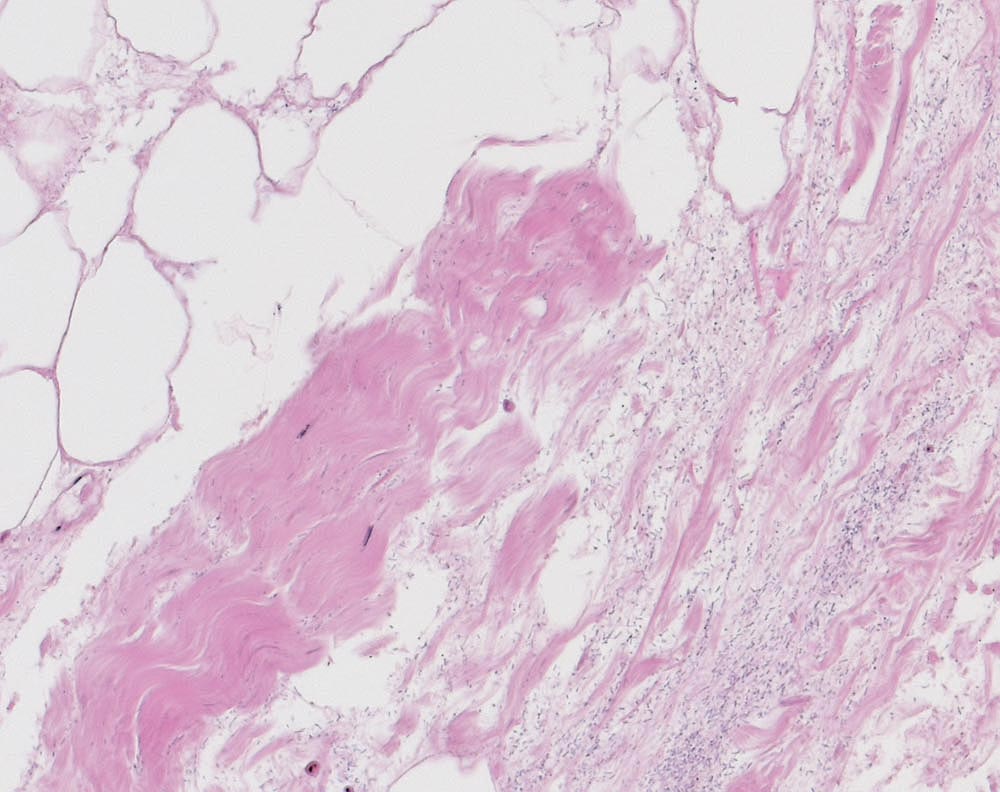

Nekrotisierende Fasziitis bei Gasbrand

Nekrotisches ödematöses Fasziengewebe und subkutanes Fettgewebe mit massenhaft Stäbchenbakterien (vereinbar mit Clostridium perfringens) und wenigen Kokkenbakterien.

Schwere, nekrotisierende Fasciitis und Myositis mit frischer hämorrhagischer Nekrose der Haut und frischen, weitgehend areaktiven Nekrosen des subkutanen Fettgewebes und der Skelettmuskulatur.